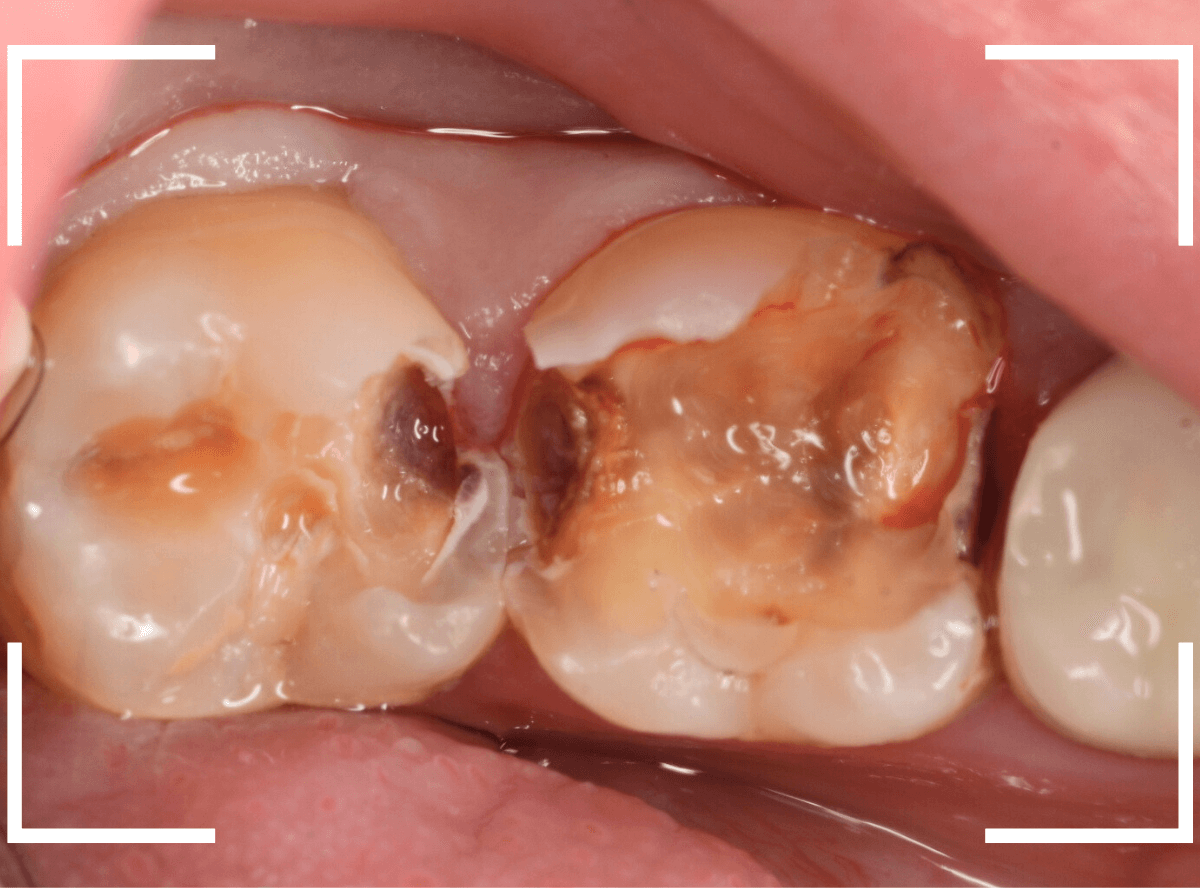

Case.23 歯のすきまから両側が大きな虫歯

「下の奥歯が痛む」という訴えで来院された患者さんのケースです。

目視でも、手前の奥歯がかけていて、中で虫歯が広がってるであろうことは予想できます。

ピンセットで歯を叩いてみても、手前の奥歯が痛むようです。

レントゲン写真で確認します。

青い線が神経、赤い線が虫歯の範囲です。

奥歯の方がより深い虫歯に見えますが、再度打診で確認したところ、やはり手前の奥歯が痛むそうです。

状況から、まず手前の奥歯から治療となりました。

麻酔をして、手前の奥歯のレジンを慎重に外します。

前に虫歯の治療をした時点で、神経スレスレの状態でしたので、削りすぎないように慎重にレジンを外さなければいけません。

レジンを外して、う蝕検知液で確認します。

レジンの中で虫歯が進行していたのがわかります。

慎重に全ての虫歯を除去しました。

何とか、神経が露出せずに済んでいます。

お薬をつめて、セメントで蓋をして経過観察します。